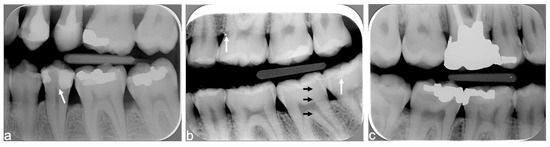

| Centering the cone with or without rectangular collimator | Image outline Tooth fully visible | Complete image outline; borders not cut No truncated image | Incomplete image outline; image cut without consequences on diagnosis | Incomplete image outline, image cut, with consequence on diagnosis |

| Centering of the digital plate | Ratio of maxillary and mandibular quadrants (visibility of teeth and alveolar crest at vertical level) | 50–50% ratio: image well centered vertically (maxillary and mandibular teeth each cover 50% of the image) | 40–60% ratio: image moderately centered vertically (one quadrant covers more than half of the image, alveolar bone visible on both quadrants) | Image not vertically centered (one quadrant covers more than 60% of the image, alveolar bone of opposite quadrant not visible) |

| Distal contact points (between canines and the 2nd lower molars) | 4 distal contact points are visible | 3 distal contact points are visible | <3 distal contact points are visible | |

| Correct bite on the film-holder | -- | Yes Upper and lower quadrants in contact with film-holder | No One quadrant without contact with film-holder | |

| Superposition of enamel (horizontal angulation) | Superposition of enamel on the contact points | Superposition <1/3 of enamel width | Superposition between 1/3 and 2/3 of enamel width | Superposition >2/3 of enamel width |

| Image contrast | Correct image contrast | -- | Yes | No (too bright or too dark) |

| Artefacts | Exposure to ambient light, presence of foreign object or vertical stripes | -- | No Or minimal without consequence on diagnosis | Yes With consequence on diagnosis |

| Intact digital plate, without traces of scratches, folds, or other | -- | No Or minimal without consequence on diagnosis | Yes With consequence on diagnosis | |

| Overall X-ray quality | Overall quality | Excellent overall quality | Acceptable quality; minor faults/errors | Major error; diagnosis made difficult |